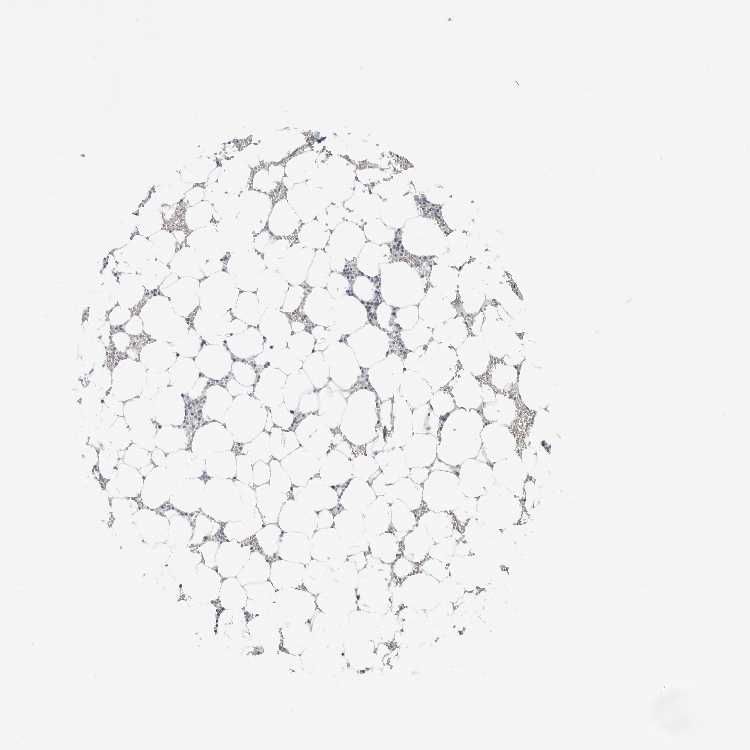

TISSUE PRIMARY DATA BONE MARROW Show tissue menu

BONE MARROW - Antibody stainingi

Antibody staining in the annotated cell types in the current human tissue is reported as not detected, low, medium, or high, based on conventional immunohistochemistry profiling in selected tissues. This score is based on the combination of the staining intensity and fraction of stained cells.

Each image is clickable and will lead to virtual microscopy that enables deeper exploration of all samples and also displays staining intensity scores, fraction scores and subcellular localization as well as patient and tissue information for each sample.

Antibody HPA027120Antibody HPA027125Antibody HPA027268

Hematopoietic cells LowNot detectedNot detected